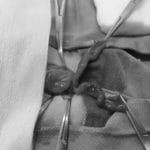

- チンチラの子宮水腫(外科手術例)チンチラは子宮疾患が多いです。 この子は食欲のムラと体重の増減が多かったため、血液検査、超音波検査などを行い、子宮が腫れていることがわかりました。 投薬にも反応がなく、子宮が腫れたままであったため、手術により摘出すること […]